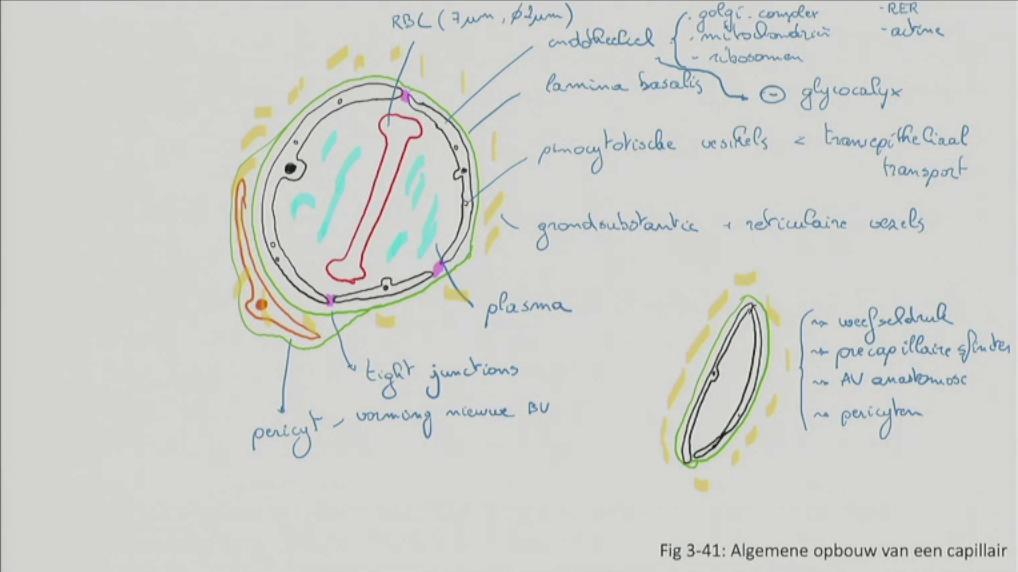

Fig 3.41: Algemene opbouw van een capillair

A gevulde capillair

-

endotheel

lamina basalis grondsubstantie + reticulaire vezels -

pinocytotische vesikels

RBC (7-9 um, 2um doorsnede) plasma tight junctions (paars) -

pericyt (oranje, vorming nieuwe bloedvaten)

B lege capillair

|